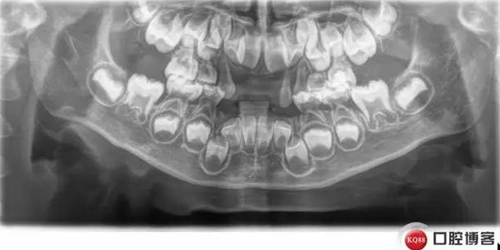

復(fù)診X線:

低磷脂酶癥是一種罕見的遺傳代謝異常,缺乏組織非特異性堿性磷酸酶活性,口腔表現(xiàn):牙齒萌出遲緩,乳恒牙均易早失,脫落牙齒的牙根長度無變化。乳前牙最易受累而早失。病程中無明顯疼痛,牙周無明顯炎癥。X線片示牙釉質(zhì)正常,髓腔和和根管增大,牙槽骨有吸收。